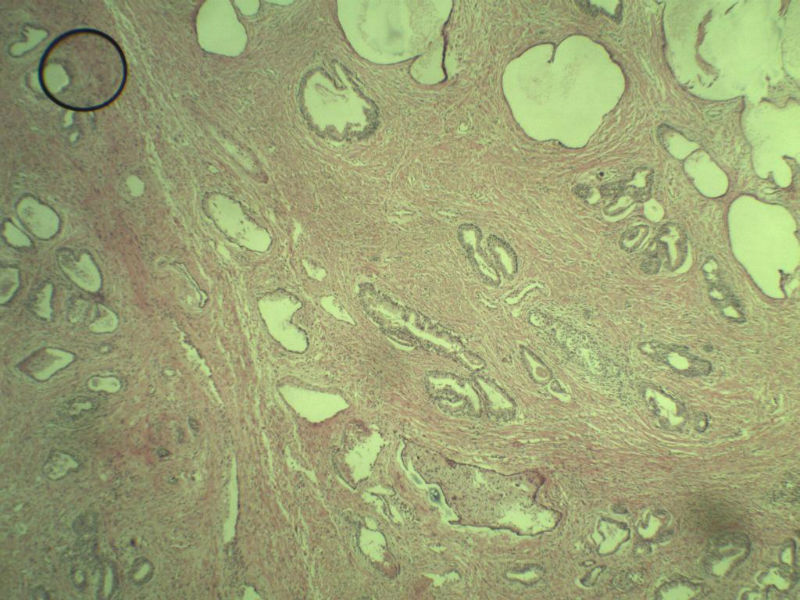

男 75岁 因排尿困难半年行前列腺切除术,体积 4 × 3 × 2.5 cm3,切面灰白,实性,质韧。请各位老师看看 有问题没? 谢谢了!

前列腺增生,有腺瘤样结节形成。

前列腺增生伴尿路上皮鳞化及Brown巢形成,未见恶性。

前列腺结节性增生

良性前列腺增生伴尿路上皮化生